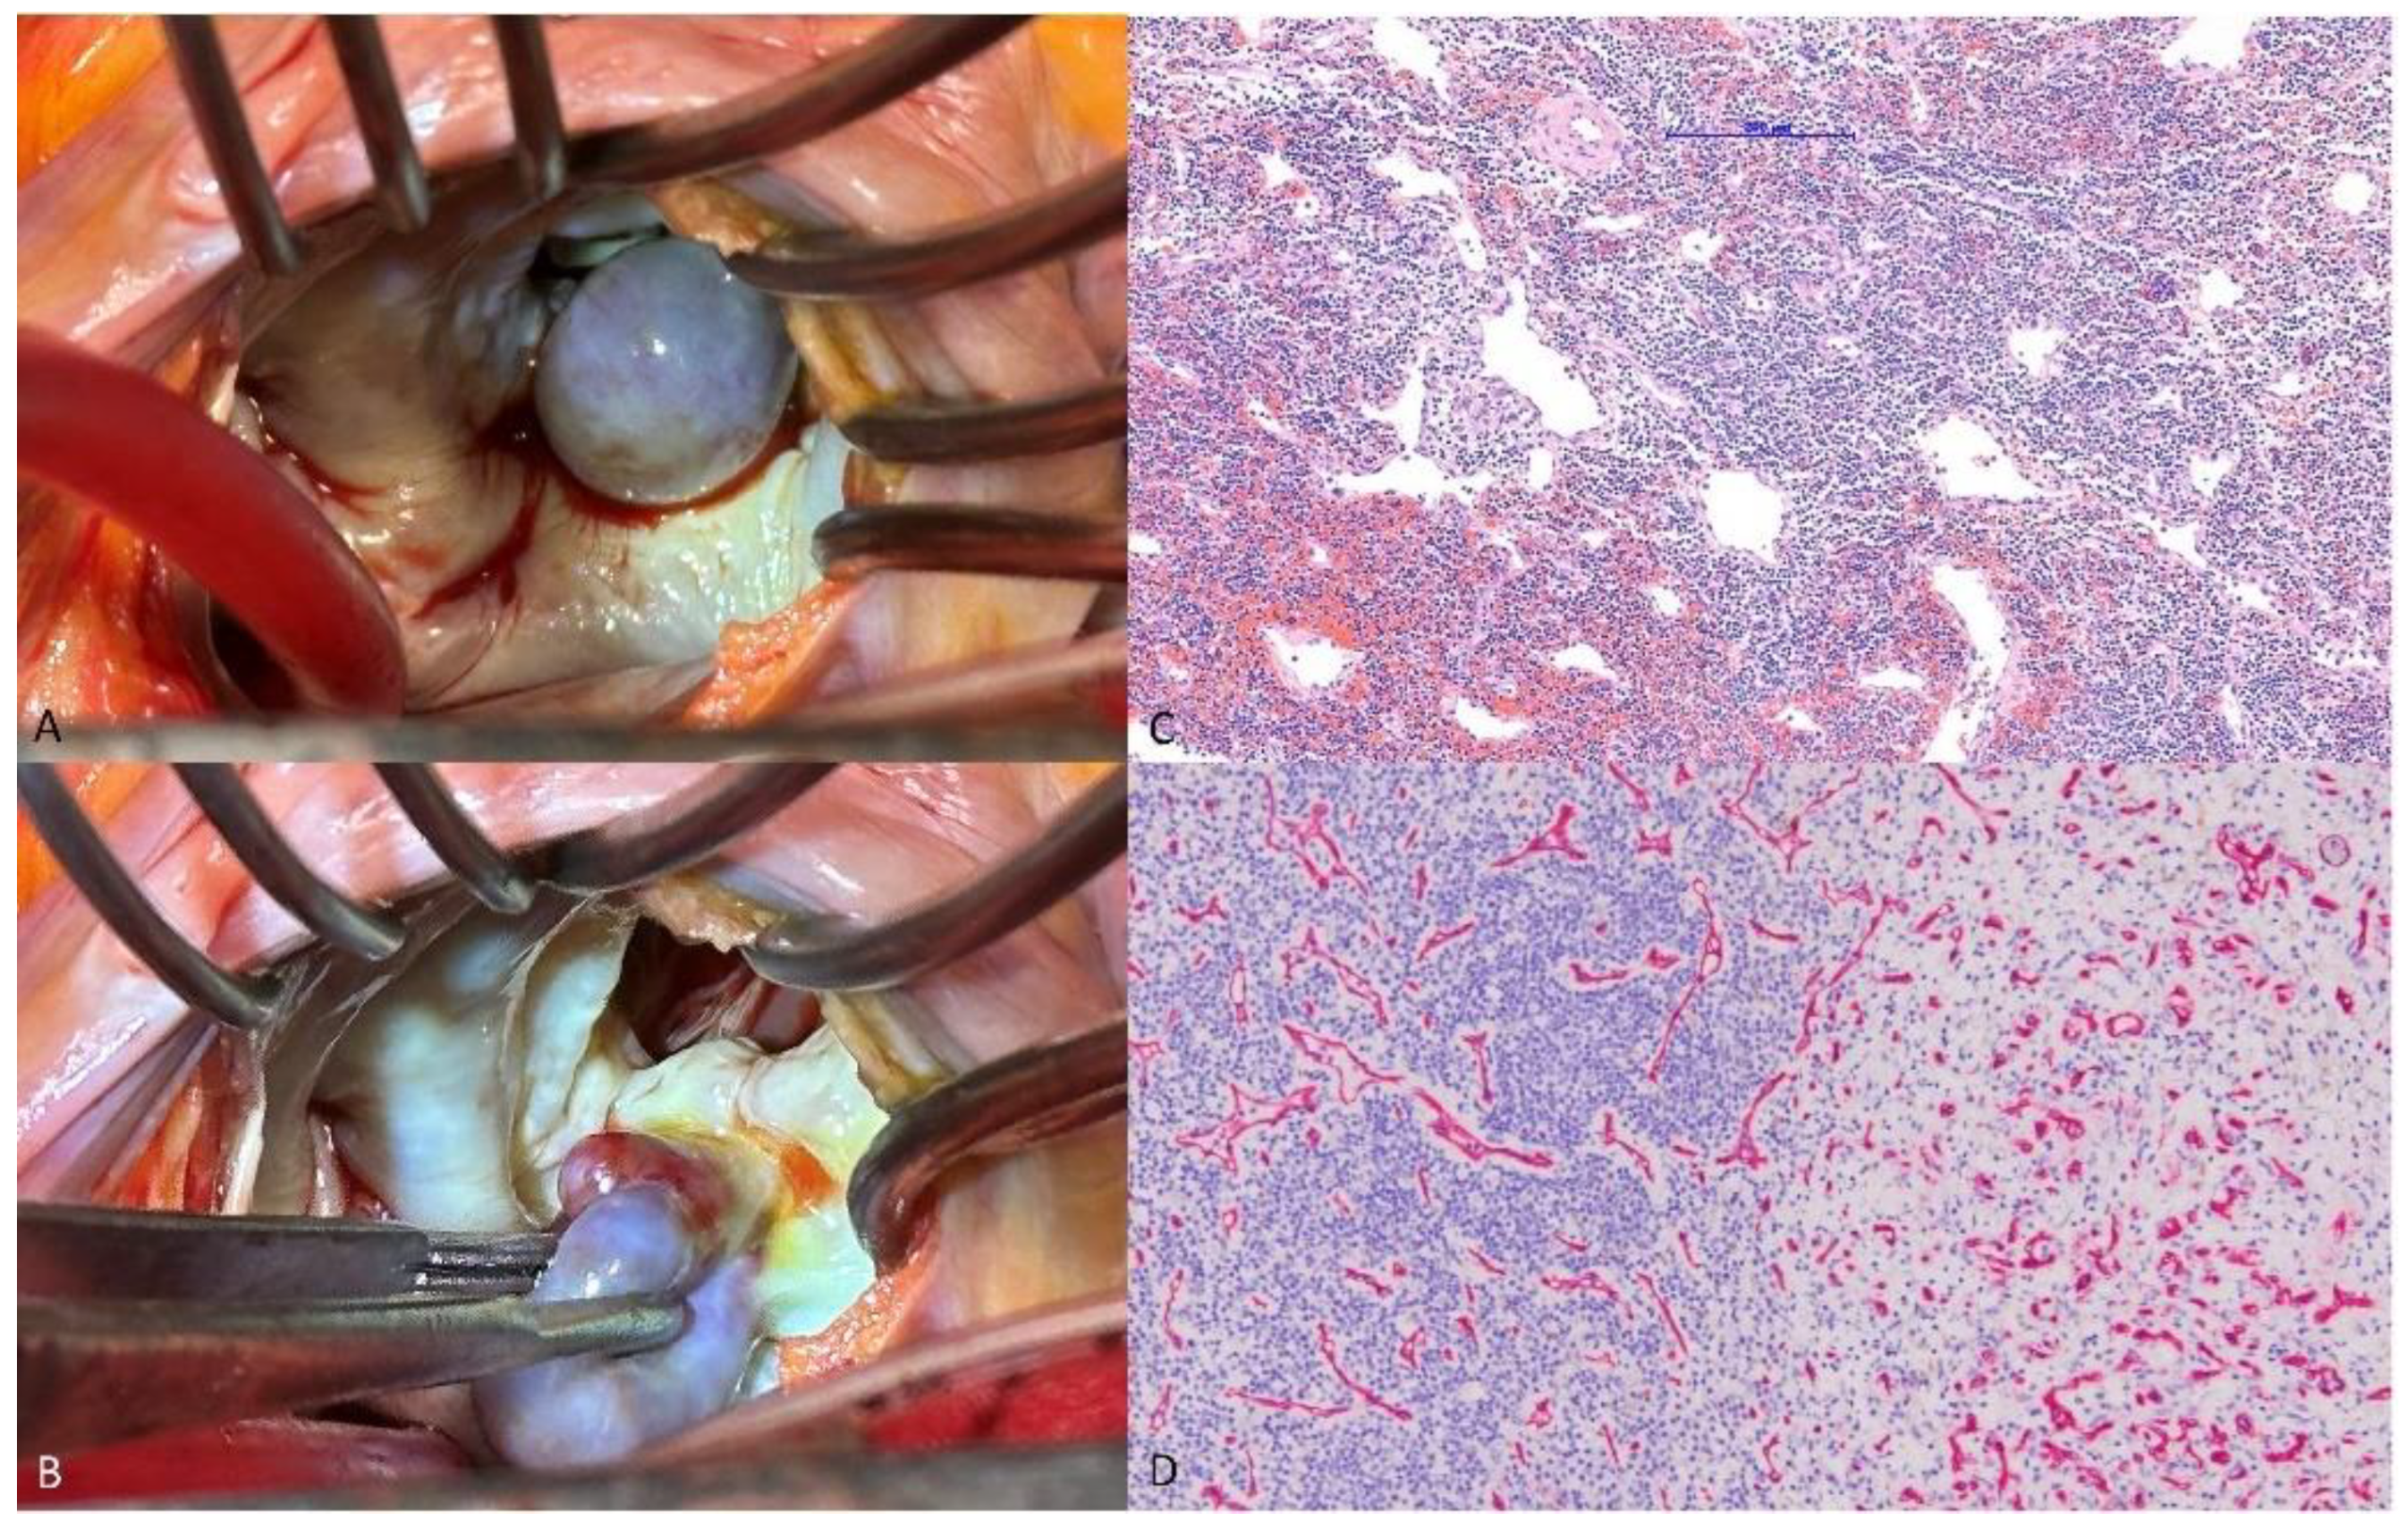

A 70-year-old man presenting with chills and cold sweats was transferred to the emergency room. An echocardiogram revealed a mobile 1.57 × 2.47 cm mass on the mitral valve (Figure 1A,B); consequently, vegetation was suspected (details in Supplementary Table S1). The laboratory tests revealed leukocytosis, elevated C-reactive protein levels, and negative blood culture (details in Supplementary Table S2). However, the echocardiologist questioned the diagnosis because of the mass’s smooth, well-defined shape (differential diagnosis in Supplementary Table S3). Transesophageal echocardiography identified a 1.9 × 1.4 cm polypoid mass with a pedicle attached to the annulus near P2, suggesting a tumor (Figure 1C,D). During surgery, a round 1.5 × 1.5 × 1.5 cm tumor was identified at the mitral annulus between P1 and P2 that was connected to underlying mitral annulus calcification (Figure 2A,B). The tumor and a small part of the annulus endocardium were excised, and a mitral ring annuloplasty was performed. Pathology confirmed the diagnosis of hemangioma with dense lymphocyte infiltrate (Figure 2C,D). Postoperative echocardiography revealed no mitral regurgitation. Previous reports have mentioned that hemangiomas on the mitral valve may cause multiple brain infarcts [3]. Other types of intracardiac tumors, such as cardiac papillary fibroelastoma, have also been misdiagnosed as infective endocarditis [4]. Through this case, we hope to offer clinicians with additional perspectives for the diagnosis and management of intracardiac mass lesions.

Figure 1. (A) Four-chamber transthoracic echocardiography view showing a mobile mass (white arrow) on the posterior leaflet of the mitral valve. (B) Parasternal long-axis transthoracic echocardiography view showing a mobile mass (white arrow) on the posterior leaflet of the mitral valve (Video S1). (C) Transesophageal echocardiography showing a 1.9 × 1.4 cm polypoid mass with a pedicle attached to the annulus near the P2 segment. The mass partially protruded into the left ventricle during diastole (Video S2). (D) Transesophageal echocardiography showing a polypoid mass with a pedicle attached to the annulus near the P2 segment. Color Doppler indicated mild mitral regurgitation. Grading of the mitral regurgitation may have been underestimated due to the mitral mass obstacle (Video S3). Preoperative coronary artery angiography showed no obvious feeding arteries (Videos S4–S6).